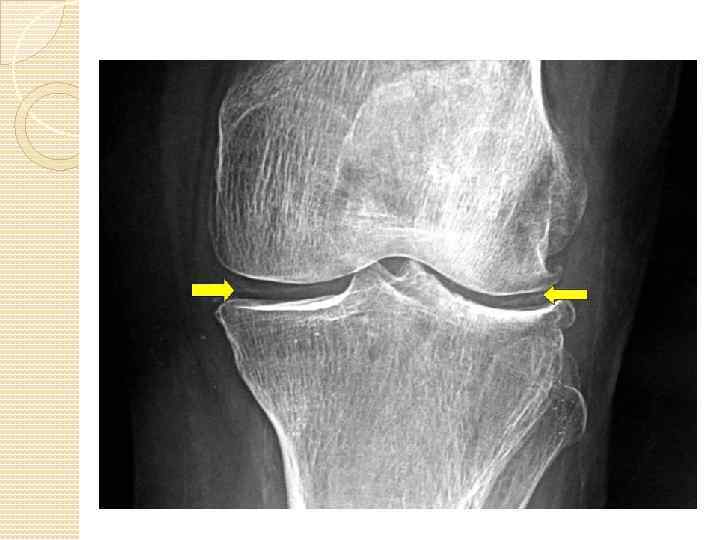

ГОНАРТРОЗ (АРТРОЗ КОЛЕННОГО СУСТАВА) Гонартроз (артроз коленного сустава) – в группе артрозных поражений суставов лидирует по частоте возникновения заболевания.

ОСТЕОАРТРОЗ Остеоартроз — заболевание, при котором изменения дегенеративного характера возникают в суставном хряще